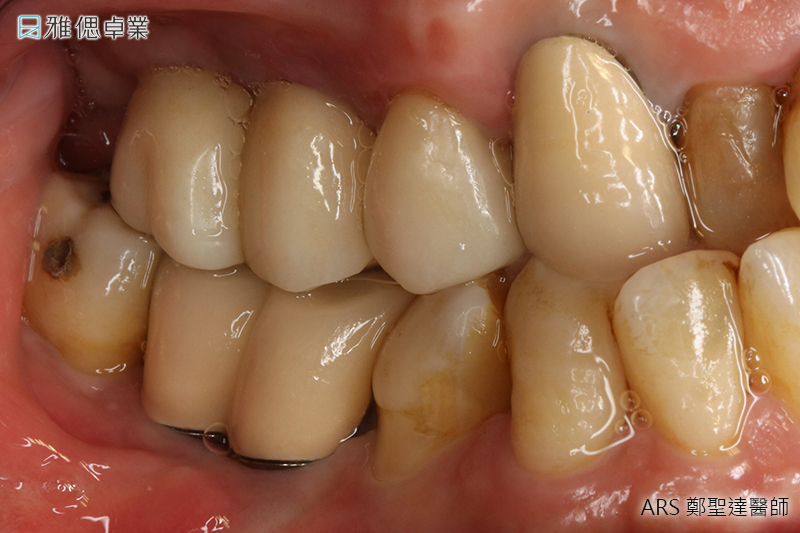

STEP6 正式牙套(正式假牙)完成

假牙會依據適合患者的咬合來做設計,若挑選全陶瓷假牙,它的高硬度及部分透光、美觀、咬合力量、高生物相容性、高密合度都會讓您照顧起來更加容易輕鬆。

人工植牙後的維護保養

假牙完成後,都需有良好的口腔衛生保養,維持良好的口腔清潔習慣,才能保持人工植牙的健康和延長人工植牙的壽命。人工植牙與自然牙一樣,需要使用牙刷、牙線及口腔清潔用品來清潔,以及定期口腔檢查。建立正確的咀嚼習慣便能延長您的人工植牙的壽命。建議每三至六個月回診洗牙,避免牙結石堆積導致植體周圍組織發炎,形成所謂的「人工植牙的牙周病」,久而久之便會導致人工植牙的失敗而掉落。